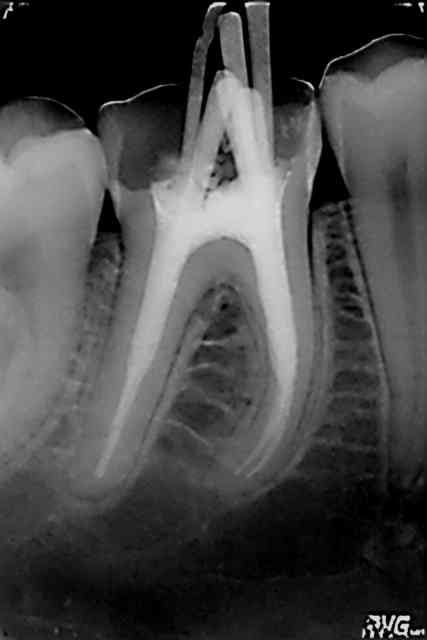

Regarde l'évolution du cas Katia sur 46 :

en 2002 , Chicot29 traite parfaitement cette dent , 10 ans plus tard sur nouveau status elle n'est plus présente , et la situation à continuée de se dégrader .

Reconstitution moignons technique directe 15/25 et provisoires , avulsion des molaires trop atteintes PAP .